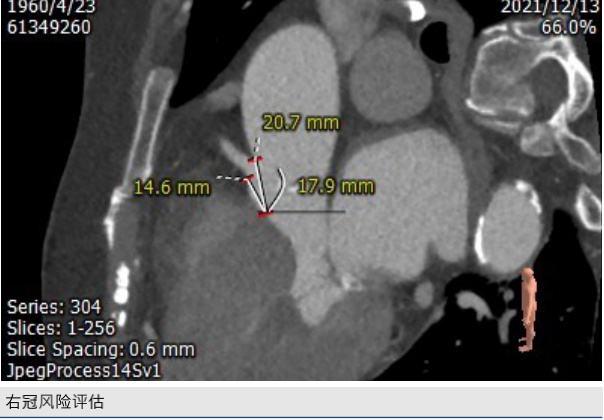

CT评估: